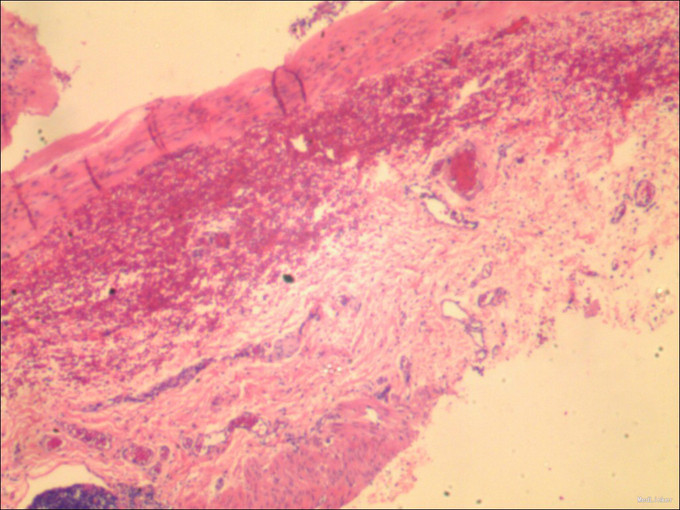

诊断:肛门狭窄术后继发性巨结肠 治疗:完善术前准备,全麻下行腹腔镜下经肛门继发性巨结肠根治术,术中见肛门往内回缩,肛周瘢痕增生明显,直肠下段扩张明显,术后给予积极抗感染补液治疗。